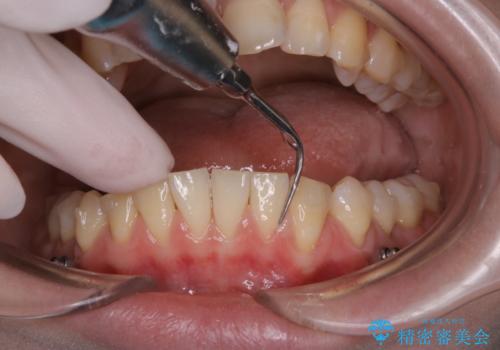

インビザライン矯正治療中のPMTC

インビザラインでの治療中の患者様のクリーニング前後写真です。

- インビザライン矯正中に茶色が気になるとのことで来院されました。PMTC30分コースを行いました。